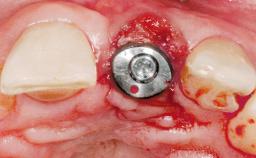

This 43-year-old male patient, a non-smoker, came to our practice because of a fracture of tooth 12 caused by a bicycle accident. Due to the combined para- and infrabony crown and root fracture, tooth extraction, and subsequent implant placement were suggested to the patient as the therapy of choice. The patient had high esthetic expectations with regard to the treatment outcome and asked for an immediate fixed provisional restoration. His individual esthetic risk profile summed up to a medium esthetic risk.